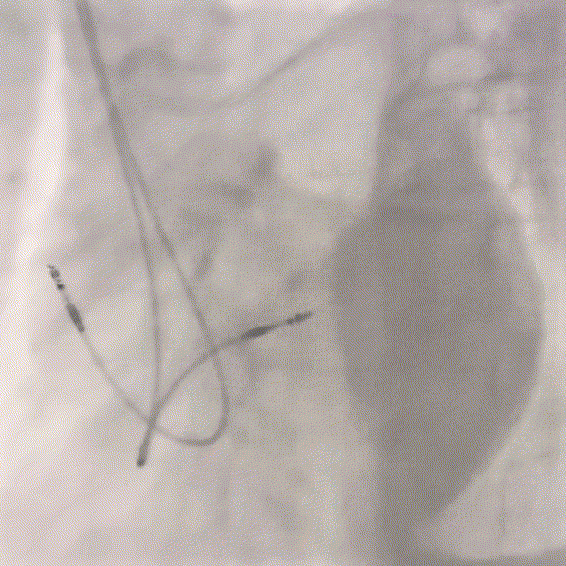

图8

图9

图10